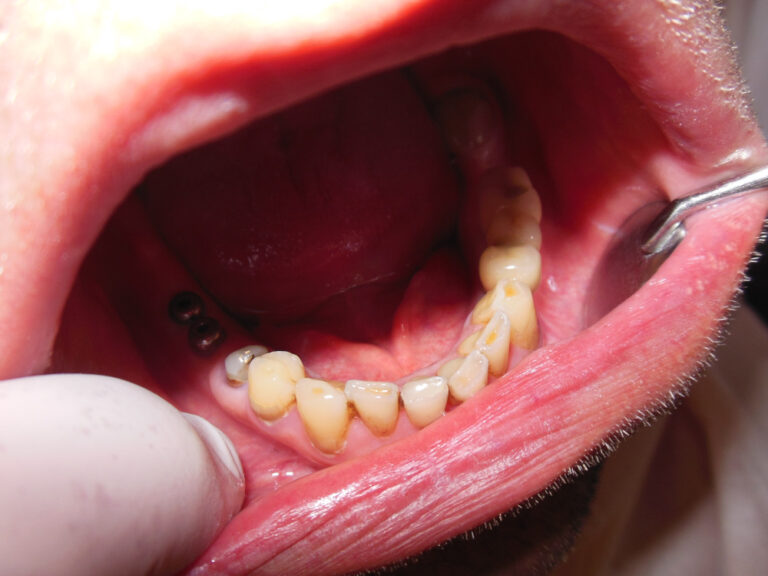

Przykłady implantologii

Zastosowanie implantoprotetyki w przypadku gdy klasyczna protetyka nie sprawdza się.